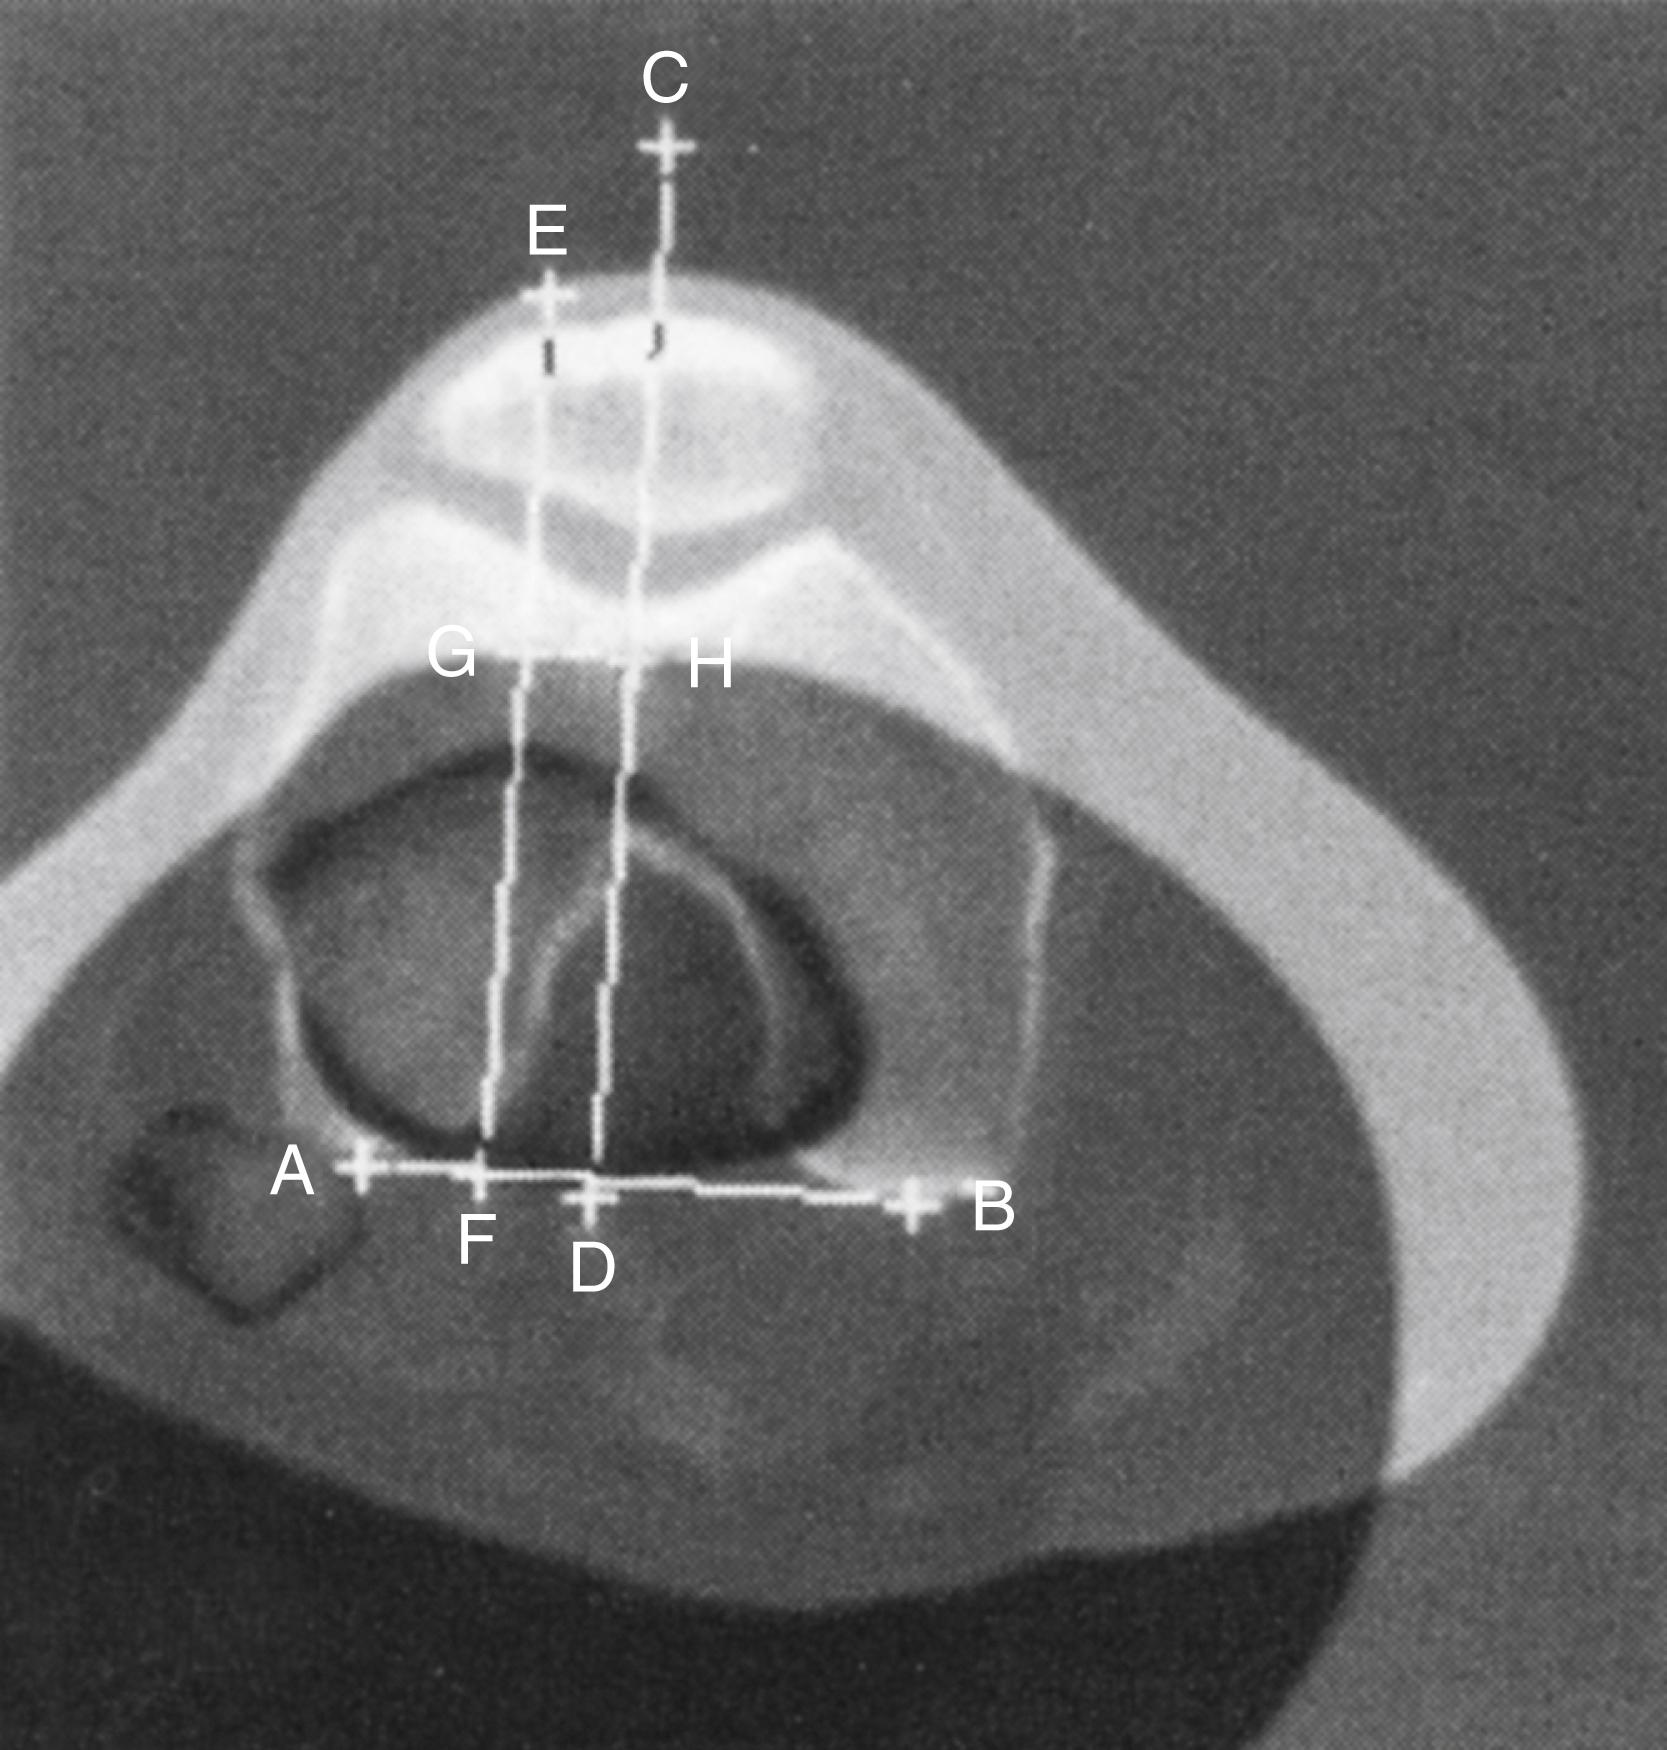

When the axial view has been obtained, the shape of the patella should be evaluated, along with the shape of the femoral trochlea and the relationship of the patella to the femur. Normally, the patella appears evenly seated within the trochlear groove of the femur, with an equal distance between both patellar facets and the adjacent femoral surfaces. Abnormalities include tilting of the patella or subluxation and complete dislocation of the patella ( Fig. 47.3 ). The trochlea is evaluated on the Merchant view for dysplasia, sulcus angle greater than 145 degrees, and congruence—normally 60 ± 11 degrees ( Figs. 47.4 and 47.5 ). For most dislocations or first-time dislocations, particularly in athletes, MRI or three-dimensional (3D) CT examination may be indicated to evaluate for chondral damage, loose bodies, dysplasia, and malalignment. An axial view at the superior trochlear groove is used to evaluate dysplasia; superimposed views are used to evaluate malalignment. Tibial tubercle–trochlear groove (TT-TG) distance of more than 20 mm on CT ( Fig. 47.6 ) or MRI may indicate malalignment and may necessitate distal realignment.

FIGURE 47.6, Lines used to calculate tibial tubercle lateralization using CT. Line is drawn on superimposed image between posterior margins of femoral condyles (AB) . Two lines are drawn perpendicular to this, one bisecting femoral trochlear groove (CD) and one bisecting anterior tibial tuberosity through chosen point in center of patellar tendon insertion (EF). Distance between these two lines (GH) is measured in millimeters.